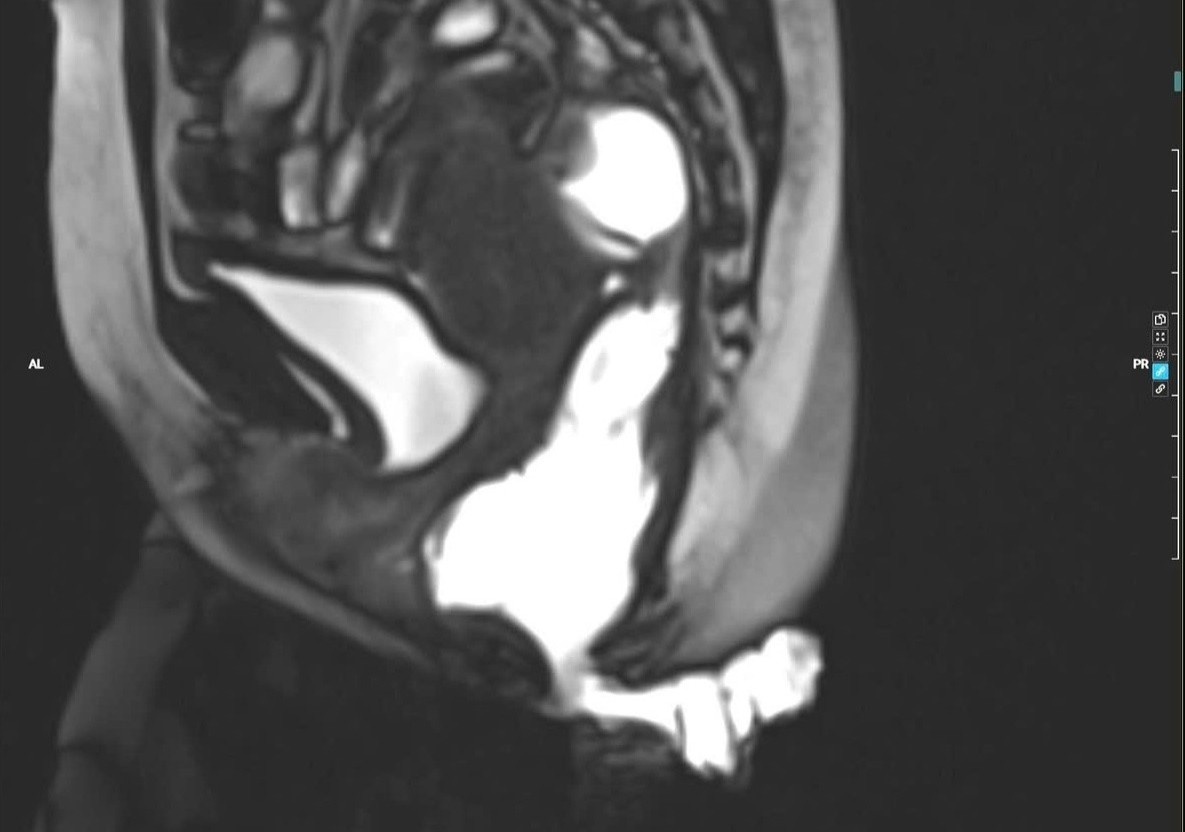

Bé trai 7 tháng tuổi mắc khối u não khổng lồ

Vượt qua cuộc đại phẫu nghẹt thở, các bác sĩ Bệnh viện Nhi đồng 1 (TP.HCM) đã bóc tách thành công khối u não phát triển thần tốc, giành lại sự sống cho bé trai chỉ mới 7 tháng tuổi.